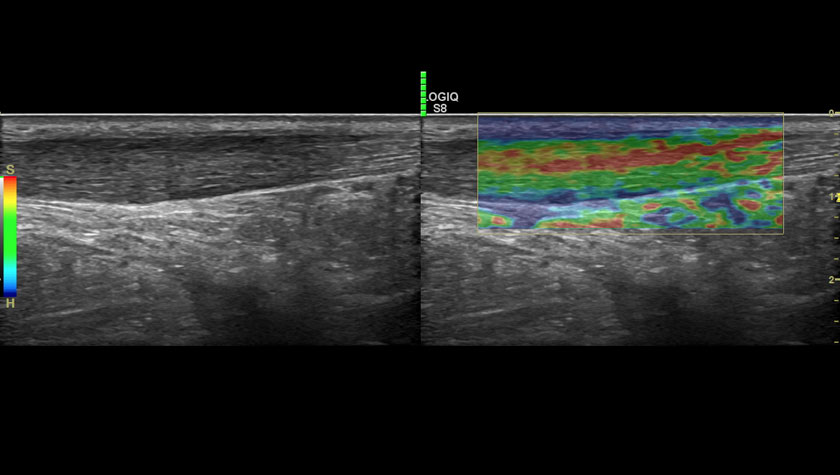

Щитовидная железа, 2D-эластография сдвиговой волны

Эластография молочной железы, датчик ML-6-15-D